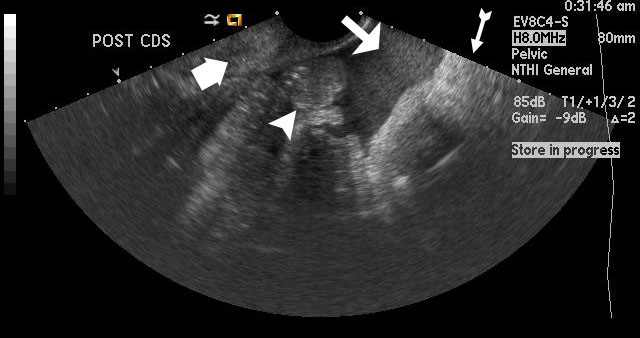

Figure 1

Uterus is empty with no gestational sac, which is concerning for ectopic pregnancy in this patient with a b-HCG level above 2000 mIU/ml. The arrows outline a central hyperechoic area that represents the normal endometrial stripe. |

Figure 5

Medium-sized arrow shows echogenic free fluid representing hemorrhage in the posterior cul-de-sac in this patient with ectopic pregnancy. The thin arrow with a tail points toward a hyperechoic structure that is the rectum, and the thick arrow points towards the cervix. The arrowhead is pointing out hyperechoic structures, which are bowel loops. |